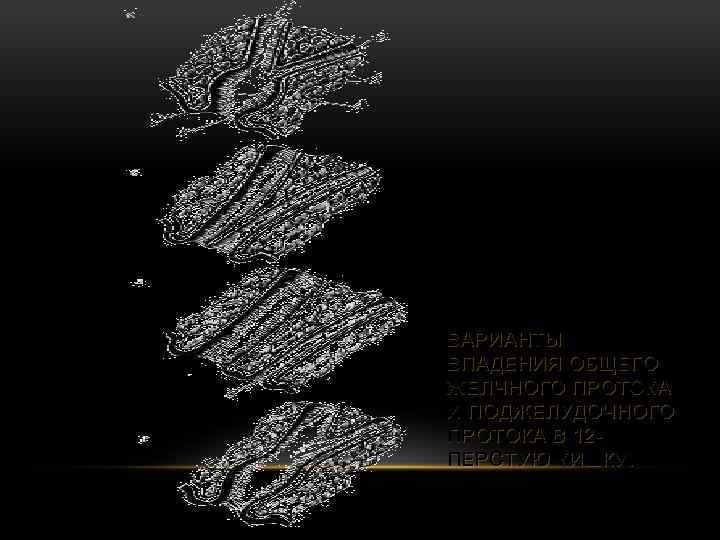

ВАРИАНТЫ ВПАДЕНИЯ ОБЩЕГО ЖЕЛЧНОГО ПРОТОКА И ПОДЖЕЛУДОЧНОГО ПРОТОКА В 12 ПЕРСТУЮ КИШКУ.

ВАРИАНТЫ ВПАДЕНИЯ ОБЩЕГО ЖЕЛЧНОГО ПРОТОКА И ПОДЖЕЛУДОЧНОГО ПРОТОКА В 12 ПЕРСТУЮ КИШКУ.